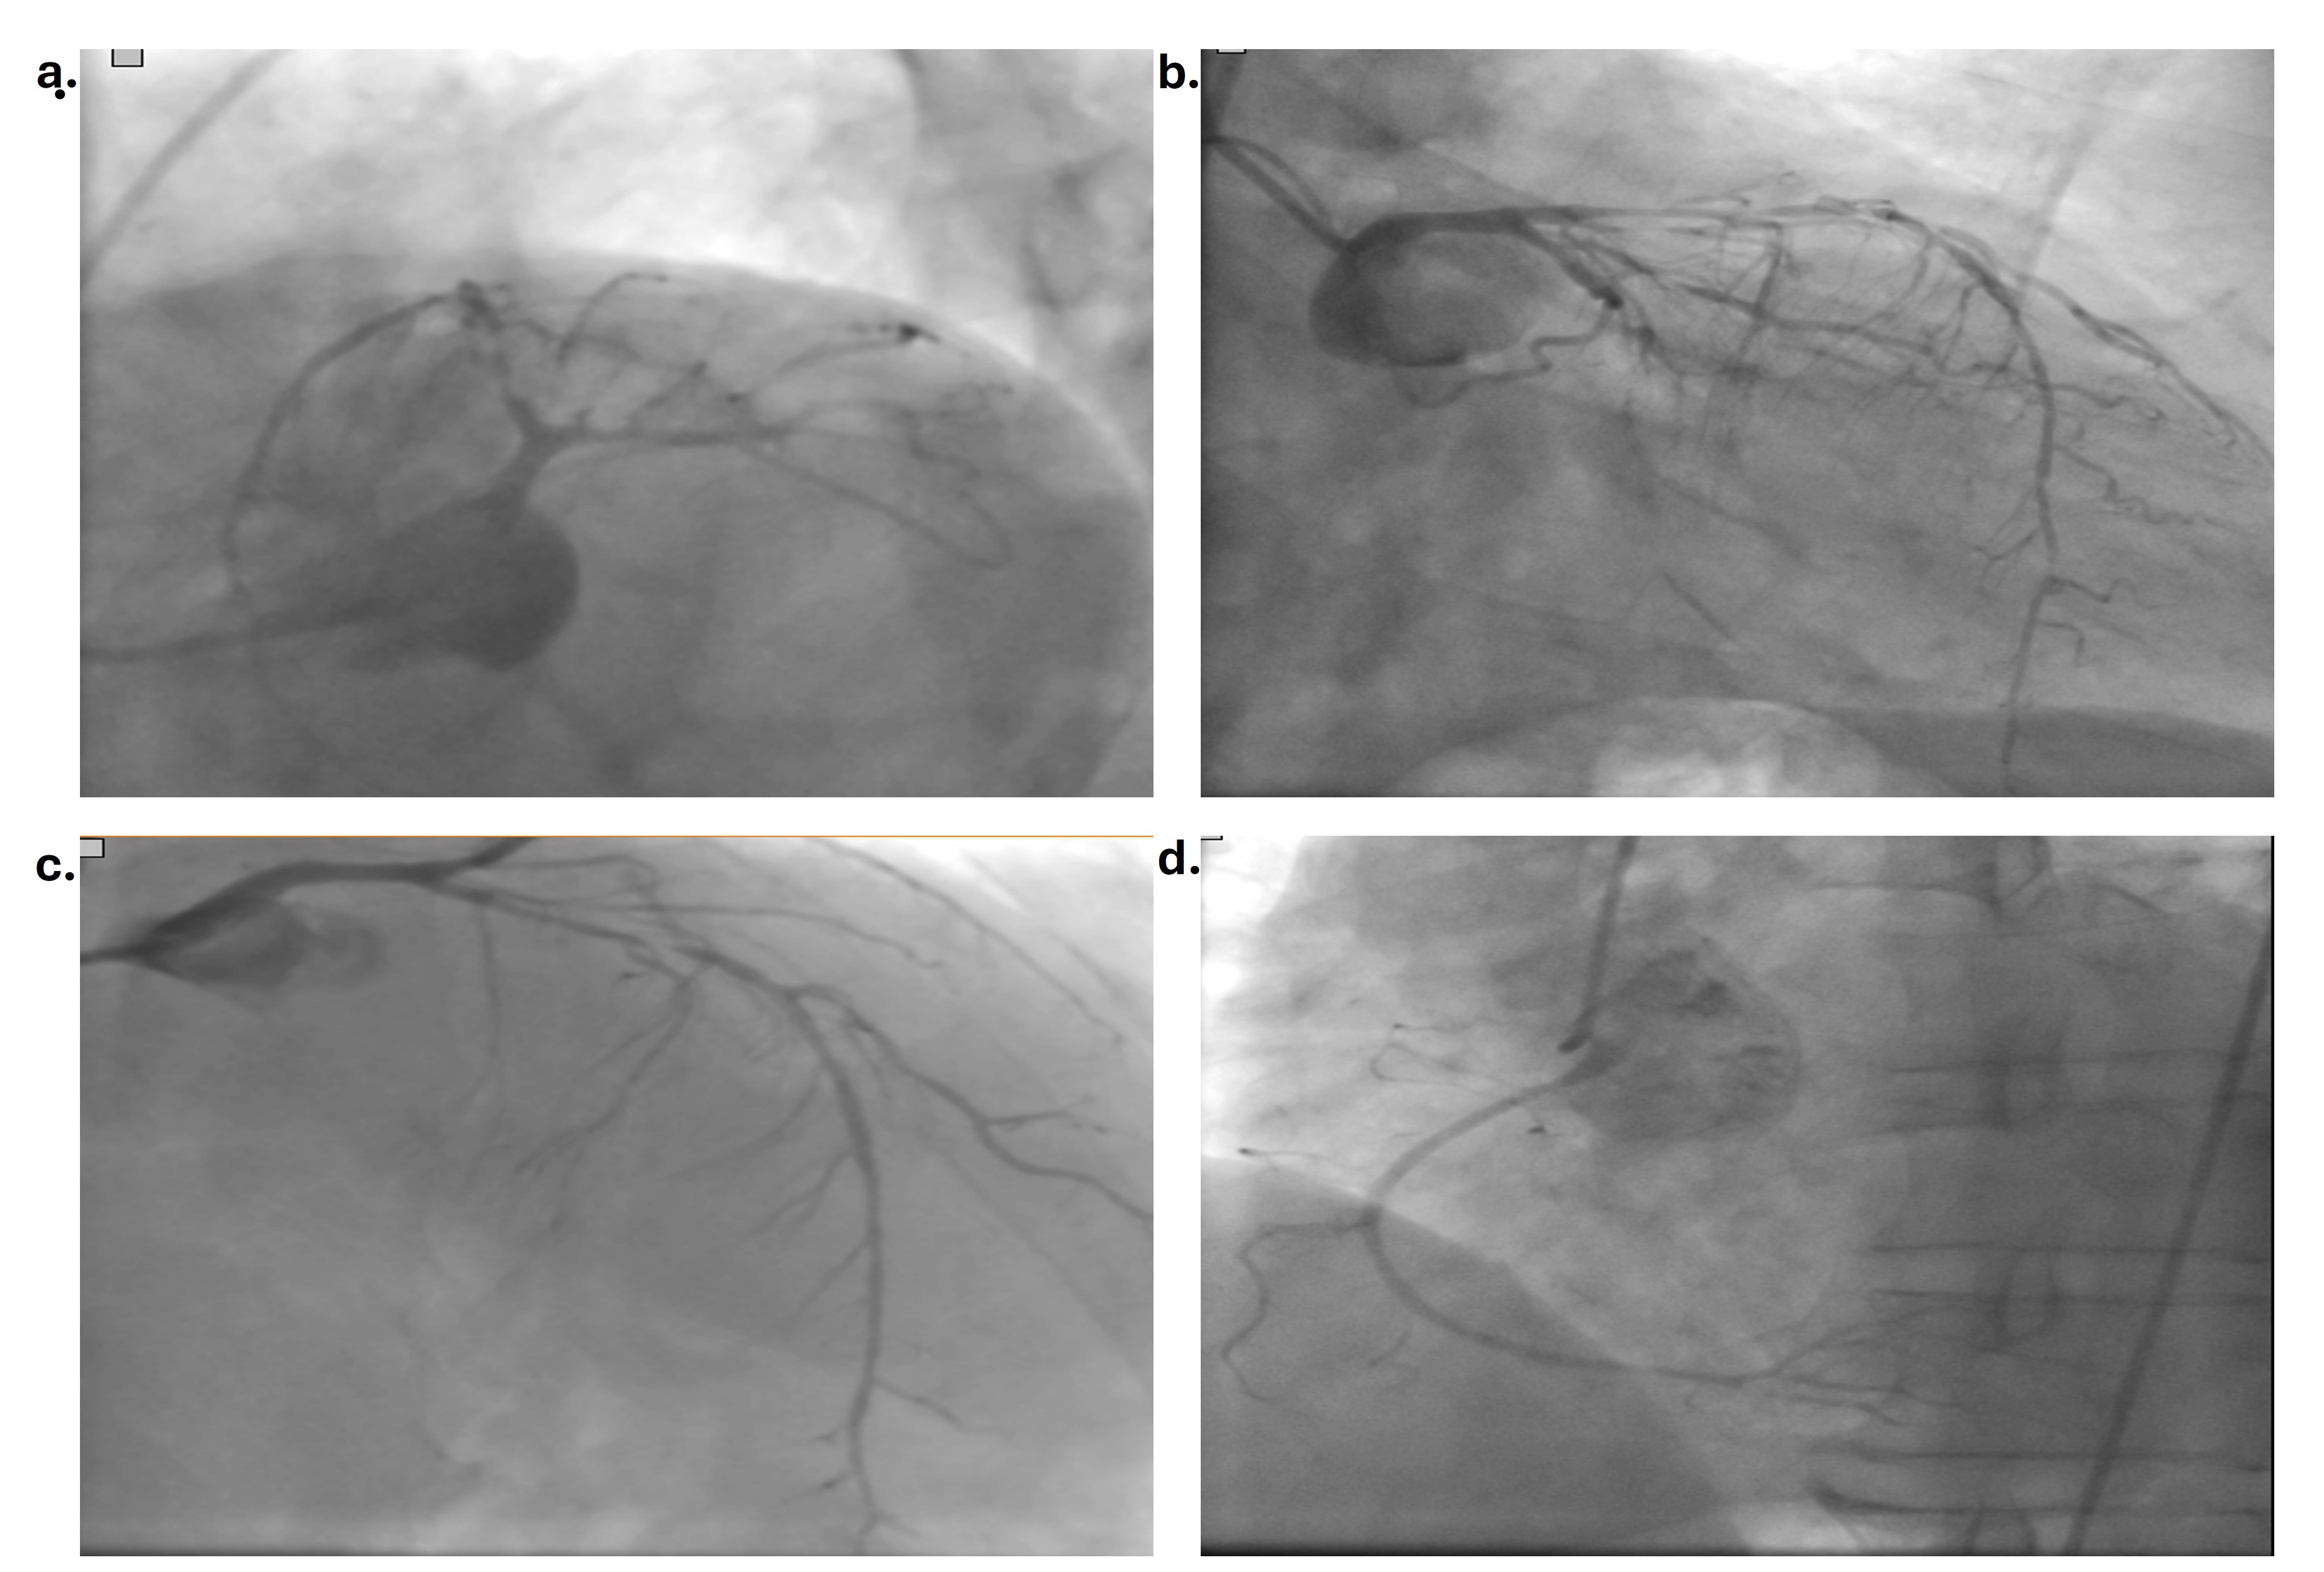

The patient was offered bypass surgery at another hospital and, after he refused, was admitted to our hospital. The patient received intravenous nitrate therapy for 4 to 6 hours after coronary angiography. He was also receiving atorvastatin, acetylsalicylic acid, metoprolol, perindopril, and enoxaparin therapy. The patient again did not accept bypass surgery; however, 48 hours later, he agreed to undergo coronary angiography for percutaneous intervention. Coronary angiography showed no critical stenosis in the LAD or Cx. There was only plaque in the LAD, and medical follow-up was planned (Figure 3) (Video 2). His cTnI value increased to 3600 ng/mL and dropped to 1000 ng/mL before discharge. There was no change in the ECG (Video 3). The patient was questioned again about drug or substance use, but he stated that he had not used anything. The blood or urine tests were not performed for substance use. The patient was discharged with atorvastatin, acetylsalicylic acid, clopidogrel, amlodipine, perindopril, and nebivolol therapy.